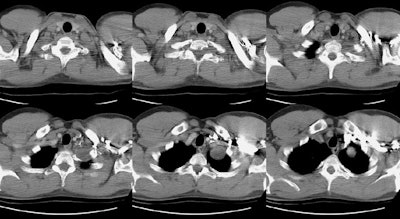

The CT scan revealed a homogeneous low density mass within the left lung apex- on careful evaluation, the mass could be seen extending outside the thoracic cavity and into the T1 neural foramena (middle image on top row and bone window shown below)